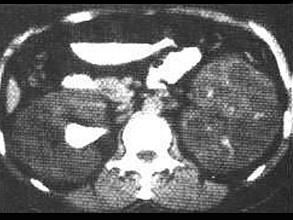

一侧肾结核无功能,对侧肾积水,其治疗原则决定于 ( )A、血尿的程度B、有无挛缩膀胱C、积水侧的肾功能情况D、全身症状E、尿频、尿急的程度

问题 一侧肾结核无功能,对侧肾积水,其治疗原则决定于 ( )

选项 A、血尿的程度 B、有无挛缩膀胱 C、积水侧的肾功能情况 D、全身症状 E、尿频、尿急的程度

答案 C